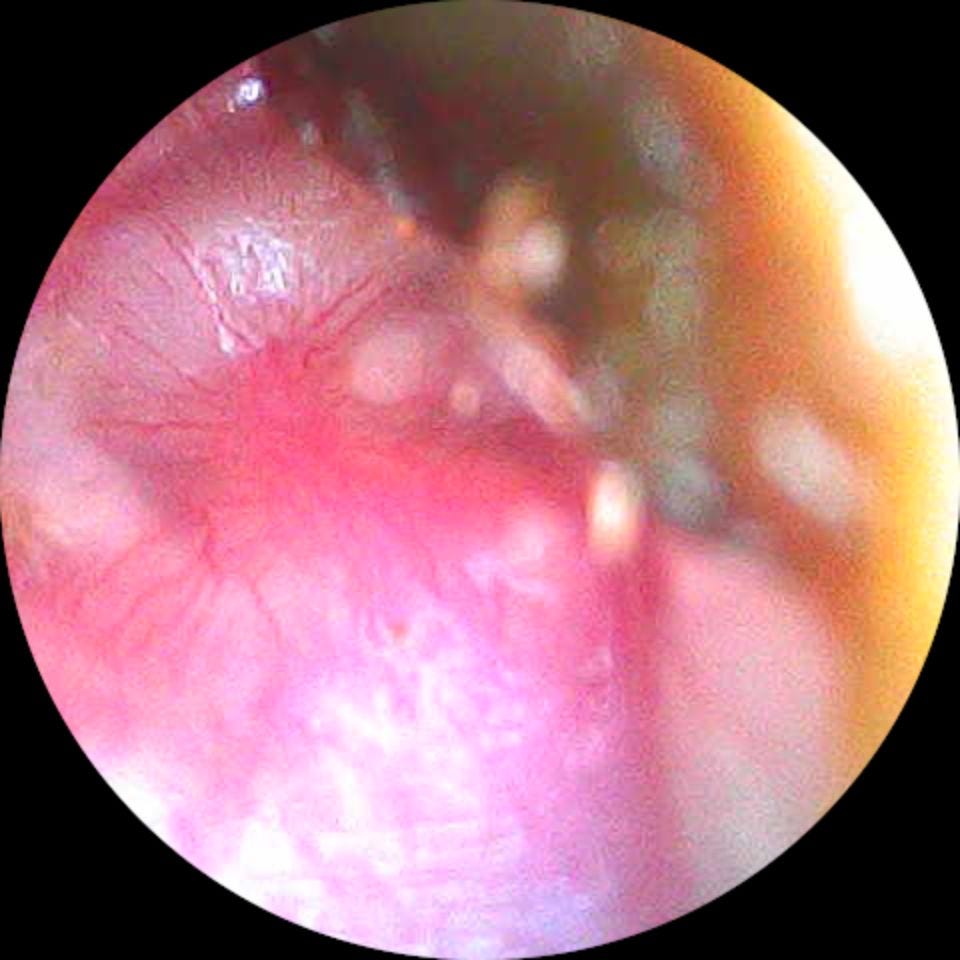

Oído Izquierdo